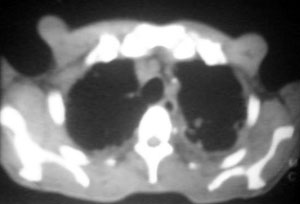

以下是引用逸风在2006-9-12 14:57:00的发言:[br]ct显示双肺上叶点片状及纤维索条状密度不均影,肺野外带近胸膜可见大小不等的含气空腔,壁略厚,境界清晰,未见液平面,中下肺野散在小片状及点状高密度影;纵隔内显示点状钙化,未见明显淋巴结肿大,构成胸廓诸骨未见明显异常.[br]诊断意见:1.双肺结核合并支气管播散;2.双肺上肺大泡.